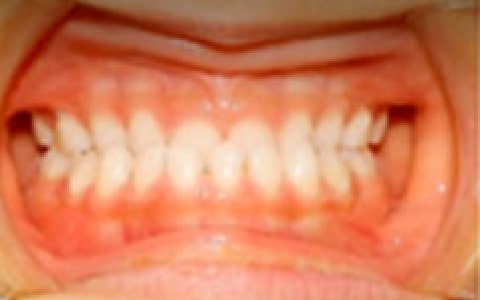

妹さん(5歳時)

妹さん かみ合わせ写真 横

妹さん かみ合わせ写真 前

妹さんも下あごが前に出ており咬み合わせが逆になっています。